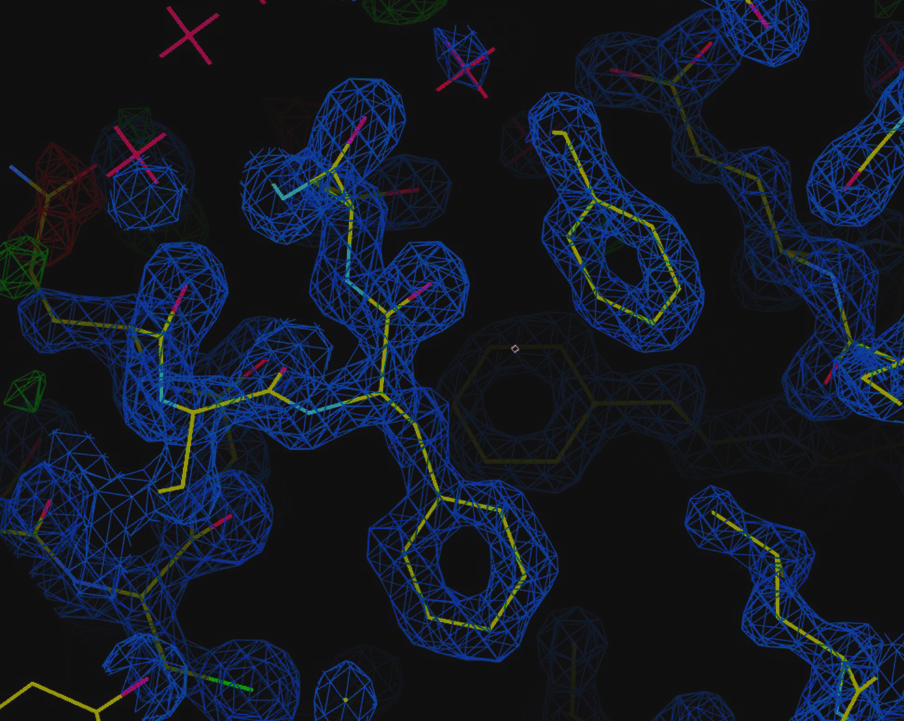

Figure 2 shows the crystal structure of a protein complex - nsp16 (MTase), and nsp10 (a cofactor) - with sinefungin (an inhibitor) bound to its active site.

MTase is a coronavirus enzyme that, when complexed with the nsp10 co-factor, plays a crucial role in RNA cap formation, making it essential for viral RNA stability. As such, the MTase complex is a promising target for antiretroviral therapy.

Using the D8 VENTURE METALJET researchers were able to model the 3D molecular structure of the complex, identifying the binding site of the inhibitor, sinefungin, which is located next to the RNA binding pocket.

Krafcikova et al., Nature Communications, Structural analysis of the SARS-CoV-2 methyltransferase complex involved in RNA cap creation bound to sinefungin.